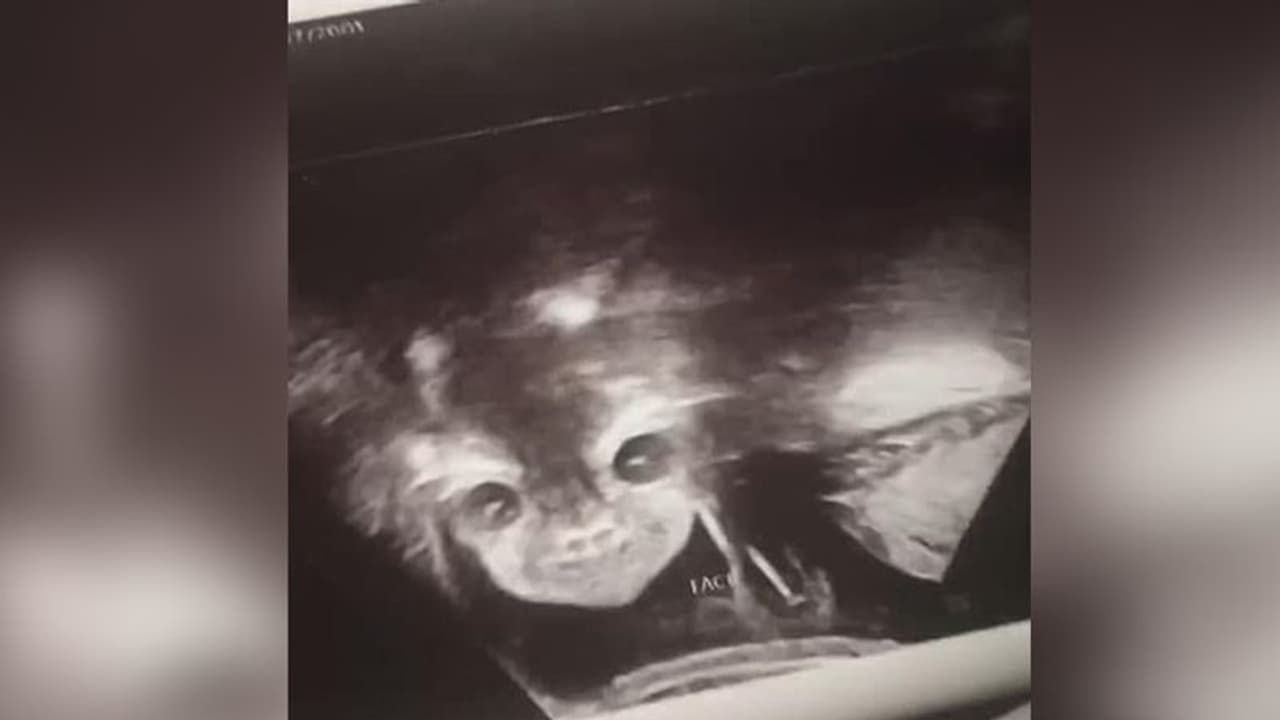

सोशल मीडिया पर एक महिला ने अपने अल्ट्रासाउंड रिपोर्ट की कुछ तस्वीरें शेयर की है। इसके बाद से ये तस्वीर इंटरनेट पर वायरल हो गई। दरअसल, 17 साल की इस प्रेग्नेंट लेडी के गर्भ में पल रहे बच्चे का चेहरा शैतान के चेहरे जैसा दिखाई दे रहा है।

इयाना ने बताया कि वो अपने होने वाले बच्चे की झलक देखने के लिए काफी एक्साइटेड थी। लेकिन स्क्रीन पर देखते ही उसकी चीख निकल गई। दरअसल, उसके गर्भ में लड़की पल रही थी। लेकिन उसका चेहरा शैतान से मिल रहा था। स्कैन के दौरान बच्ची ने आंखें खोल रखी थी। जिसे देख इयाना काफी घबरा गई।

हालांकि, बाद में नर्स ने इयाना को बताया कि बच्ची बिल्कुल नार्मल है। और इसे लेकर चिंता करने जैसी कोई बात नहीं है। इसके बाद इयाना ने अपने पार्टनर के साथ मिलकर इस मोमेंट को एन्जॉय किया। घर वापस आने के बाद इयाना ने बेबी के स्कैन की इमेजेस सोशल साइट्स पर शेयर की, जहां से ये वायरल हो गई। लोगों ने इस फोटो पर कई कमेंट्स किये। कई लोगों ने इसे देख हैरत जताई। तो कई लोगों ने इसे भगवान का करिश्मा ही बताया।